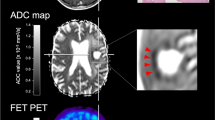

Although several advanced MRI techniques have been investigated to characterize structural, metabolic, or vascular features of brain tumours, the diagnostic performance of PET and MRI alone remain restricted. With the increasing clinical availability of hybrid PET/MRI systems and recommendations for the synergistic use of amino acid PET and MRI [18], there is urgent need for the development of neuroimaging techniques that integrate metabolic and microstructural data into biological determinants, characterising the heterogenous tumour environment (see Fig. 1, panel a), and, thereby, guide precision diagnostics and the non-invasive detection of cancer. Therefore, we established a methodology for combined and integrative multimodal PET/MRI analysis, targeting the microstructural characterization of the metabolically active tumour environment. Using metabolic imaging for the definition of 18F-FET-active tumour margins (see Fig. 1, panel b), we investigated microstructural diffusion markers of distinct metabolic compartments and evaluated the diagnostic potential of this integrative PET/DKI approach for the detection of glioma relapse and IDH genoty** in a patient cohort previously treated for glioma.

Microstructural disarray in the glioblastoma microenvironment. Advanced diffusion techniques can determine microstructural tissue properties (a) in relapsing cancer. Due to a dysregulated cancer metabolism, the glioblastoma microenvironment is transformed into a hypoxic, acidic and nutrient-depleted milieu. While central regions of highly aggressive tumours typically present necrotic features, the periphery shows higher proliferation rates due to increased vascularity in response to angiogenic stimuli and, therefore, improved nutrient/oxygen supply and metabolic waste disposal. Blood–brain barrier (BBB) impairment is accompanied by vasogenic oedema, deposition of plasma proteins or the occurrence of haemorrhage at microvascular disruption. Tumour infiltrating leucocytes aggregate in the tumour parenchyma and periphery, where a distinct immune microenvironment of CNS-resident and peripheral immune cells is established, that can inhibit or promote cancer development and growth. Multimodal data from hybrid PET/MRI (see b) combining CE-MRI, 18F-FET PET and DKI — acquired in a single session in clinically practicable acquisition time — is demonstrated in recurrent glioma, which presents a mismatch between contrast enhancement and 18F-FET-active tumour. As amino acid PET is known to provide more accurate information on the tumour extent compared to CE-MRI, we determined microstructural diffusion markers in metabolic compartments defined by 18F-FET uptake in a combined and integrative PET/DKI approach. Haematoxylin and eosin (H&E) staining from the same patient confirms recurrence (magnification 400-fold). Patients with suspected cancer relapse that received concurrent PET/MRI between 2019 and 2021 were retrospectively investigated. BBB, blood–brain barrier; HGG, high-grade glioma